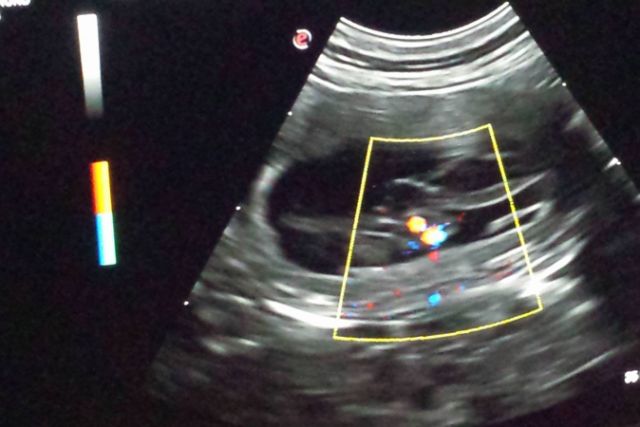

24.02.2017 9. Trächtigkeitswoche – wie viele B-linge das wohl werden? Hedlund hat nochmal sehr gut zugelegt. Ihr gehts prächtig und sie hat mega Appetit.